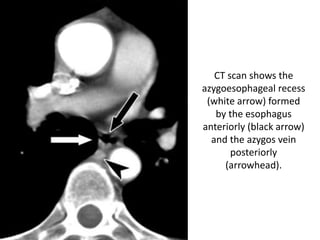

CT scan shows the

azygoesophageal recess

(white arrow) formed

by the esophagus

anteriorly (black arrow)

and the azygos vein

posteriorly

(arrowhead).

CT scan showsthe azygoesophageal recess (white arrow) formed by the esophagus anteriorly (black arrow) and the azygos vein posteriorly (arrowhead).